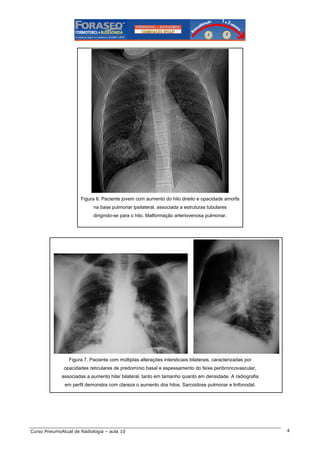

Figura 6. Paciente jovem com aumento do hilo direito e opacidade amorfa

na base pulmonar ipsilateral, associada a estruturas tubulares

dirigindo-se para o hilo. Malformação arteriovenosa pulmonar.

Figura 7. Paciente com múltiplas alterações intersticiais bilaterais, caracterizadas por

opacidades reticulares de predomínio basal e espessamento do feixe peribroncovascular,

associadas a aumento hilar bilateral, tanto em tamanho quanto em densidade. A radiografia

em perfil demonstra com clareza o aumento dos hilos. Sarcoidose pulmonar e linfonodal.